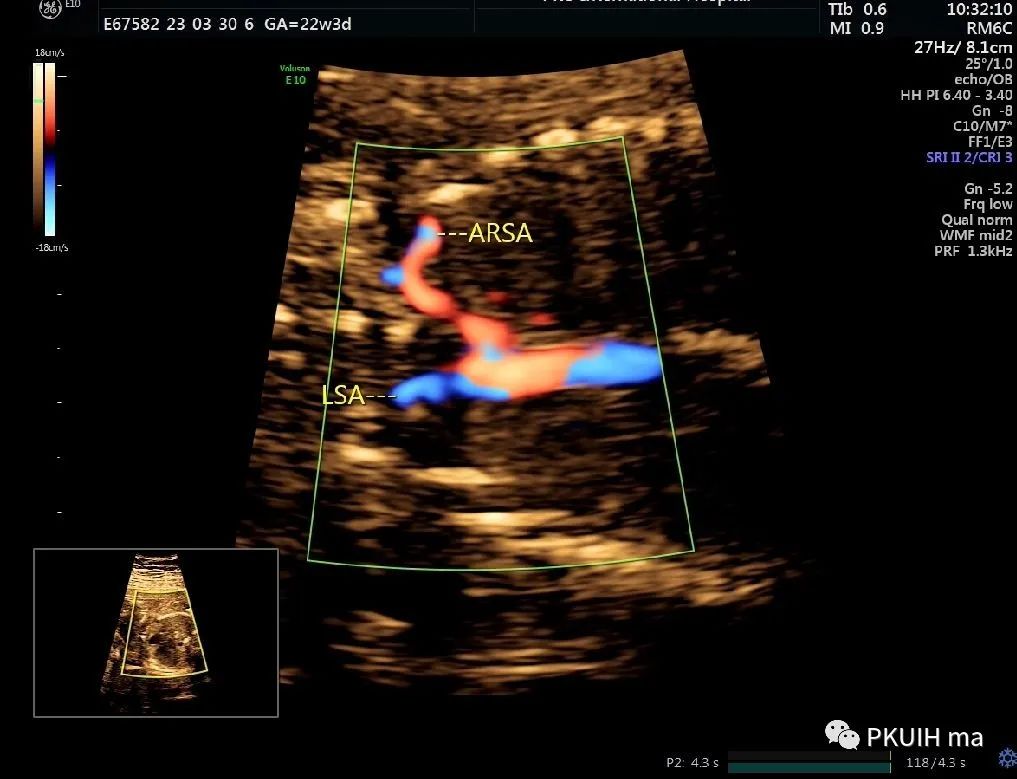

冠状切面显示右锁骨下动脉起于主动脉弓降部(ARSA:迷走的右锁骨下动脉,LSA:左锁骨下动脉)

主动脉弓走行于气管的右侧,与左位的动脉导管形成“U”型环(不完全血管环),包绕气管和食管。主动脉冠状切面可见左锁骨下动脉起自于主动脉弓降部,向左肩部走行。

右弓左导管是左位主动脉弓在左锁骨下动脉与左颈总动脉起始处之间退化,形成右弓,左位动脉导管存在于左锁骨下起源区域,右位动脉导管退化,从而形成左向右环绕气管的血管环。右位主动脉弓依次发出左颈总动脉、右颈总动脉、右锁骨下动脉及迷走的左锁骨下动脉。在个别情况下,左锁骨下动脉也可以通过Kommerell憩室的动脉管道直接起源于降主动脉。右位主动脉弓可以是复杂先心的一部分,也可以孤立存在。三血管气管切面是诊断右位主动脉弓的重要切面,结合血流显像可以鉴别右弓的三种类型。